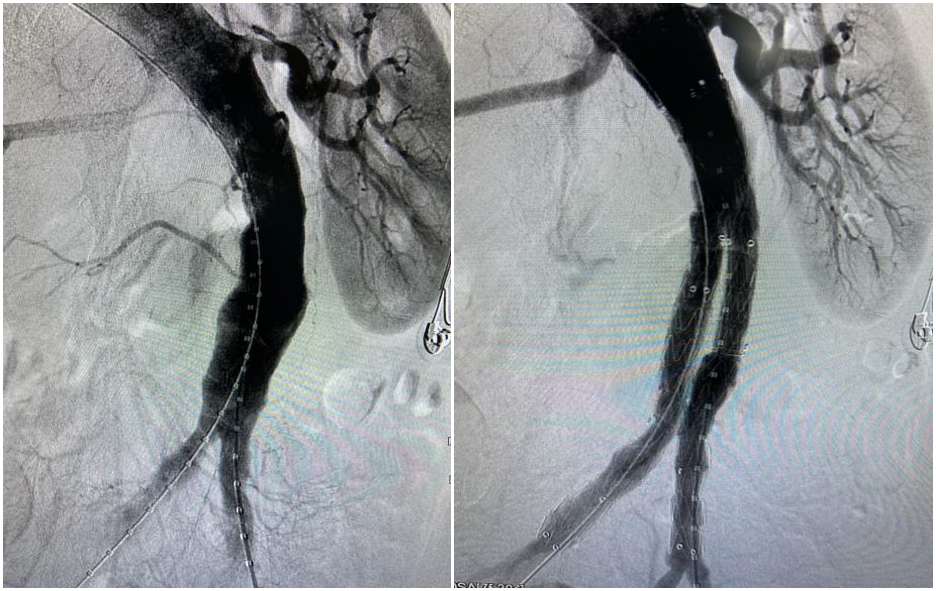

術中造影:支架術后血流通暢無內漏

術中,石建軍帶領血管病外科團隊憑借豐富的臨床經驗與穩健的技術功底,經過不到一小時的時間,為白大爺完成了手術。